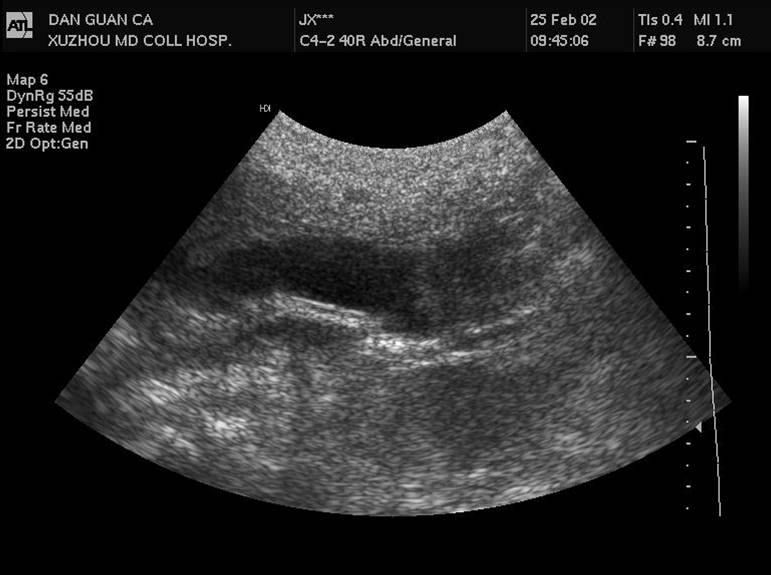

1 胆管结石